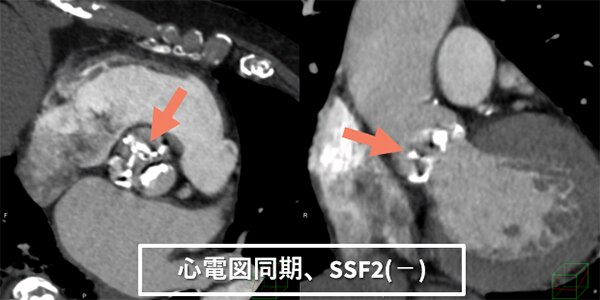

過去の検査時はどうしても至適心位相を探すため、segment再構成等を繰り返し撮影と画像検索を両立するのは困難でした。しかし、最適心位相検索に「Smart Phase」、モーションアーチファクトを抑制する 「SnapShot Freeze2.0(以下SSF2)」を併用することにより、最適心位相の検索をほぼ自動で行えるようになりました。結果、心臓CTの最適心位相検索に時間を割く必要がなくなり、人員配置の最適化を行えるようになると考えています。